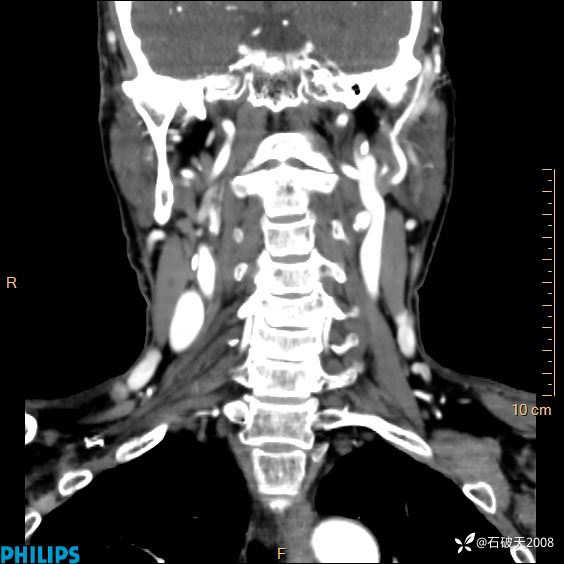

平扫